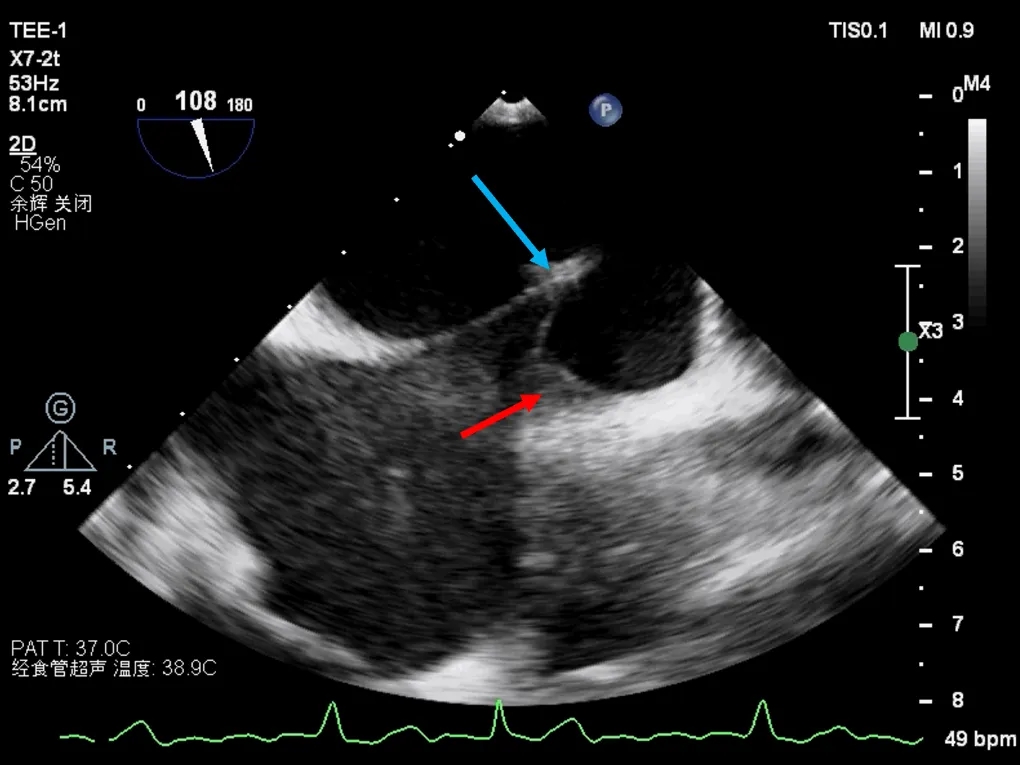

多学科讨论,为了尽可能降低卒中发生风险,平衡卒中与出血的矛盾,决定采取同期完成左心耳封堵与ASA/PFO封堵的“一站式”策略,穿刺点选择是该介入治疗的关键。在TEE实时引导下,选择ASA中心为穿刺点,并未经PFO进入左心房。这样不仅可改善左心耳封堵的同轴性,还可实现对ASA及PFO的完整覆盖,避免人为制造新的房间隔缺损。

TEE引导下的房间隔穿刺